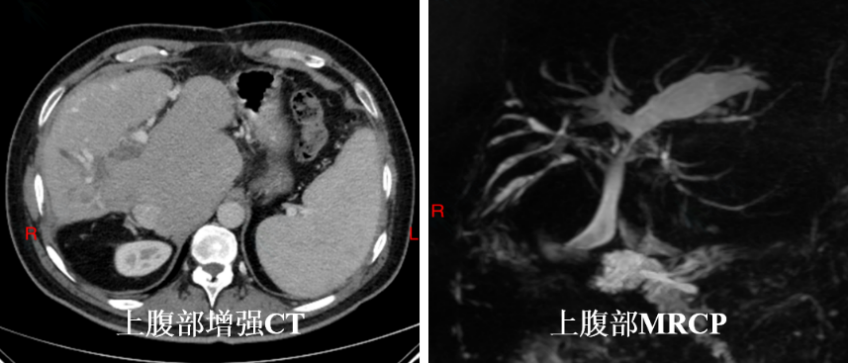

辅助检查:周先生上腹部增强CT提示肝脏形态异常,肝总管、胆总管显示不清,考虑术后改变;肝硬化,门静脉增宽,脾大。肝右叶斑片状弱强化影,肝内胆管扩张,肿瘤性病变可能。MRCP示肝内胆管扩张,肝门部胆管及胆总管显示不清。实验室检查:CA19-9 86.8U/ml,CA-125 33.1 U/ml,总胆红素48.7umol/L,直接胆红素 30.3 umol/L。